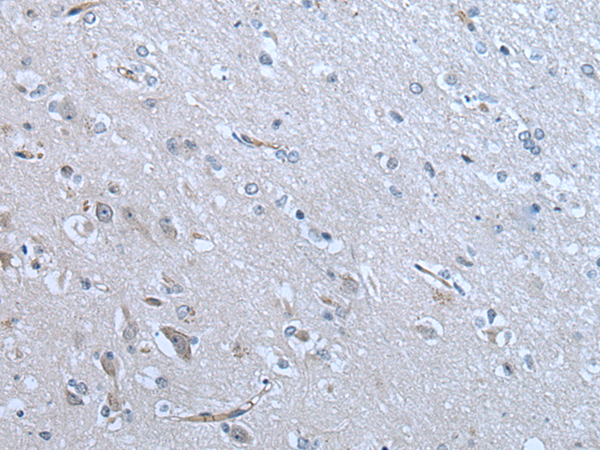

分类: 科研抗体货号: P12836别名: C19orf7应用: IHC反应种属: Human, Mouse